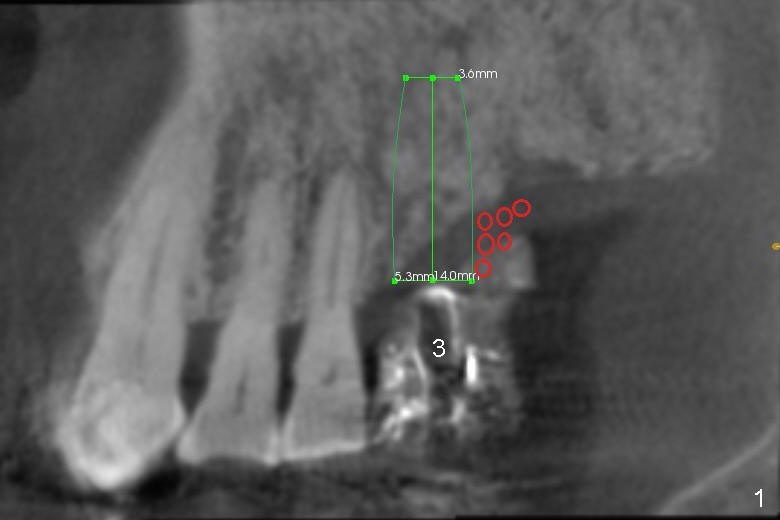

First molar occlusion is planned (1,2). The tooth #3 was extracted a year ago (Fig.1 (CT sagittal section). There is more bone loss distally so that bone graft (red circles) is required post implantation (5.3x14 mm). Buccolingual width is not severely compromised (Fig.2 (coronal section), 3).